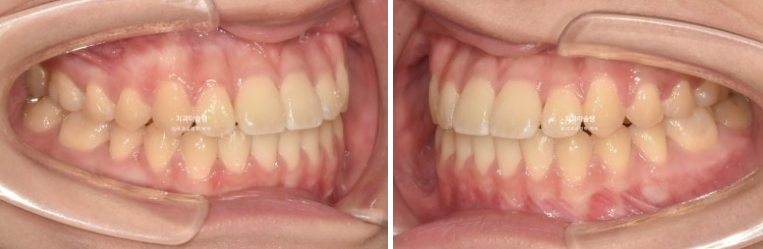

그렇게 치료를 이어가 25년 7월 드디어 치료 마무리가 되었습니다.

25.07

중심선은 정확히 맞고

양측 어금니는 1급 교합 관계를 보입니다.

이제 전 후 비교 보겠습니다.

총 치료기간은 1년 10개월 입니다.

개방교합은 해소가 되었습니다.

교합은 1급 교합관계를 보입니다.

아랫니가 뒤로 들어가면서 앞니가 거꾸로 물리는 상태 즉 반대교합은 해소되었습니다.